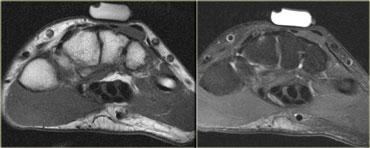

Hình bên trái minh họa một loại cơ phụ thường gặp: cơ dép phụ.

Thông thường, cơ dép bám gần như hoàn toàn vào gân Achilles, với một gân dép nhỏ đi phía trước gân Achilles.

Tuy nhiên, ở khoảng 1-2% dân số, cơ dép đi xuống và bám trực tiếp vào xương gót.

Tình trạng này biểu hiện như một khối có thể sờ thấy và thường, nhưng không phải lúc nào cũng, xuất hiện hai bên.

Hình bên trái cho thấy một cơ dép ở vị trí thấp, nhưng không có điểm bám gân riêng biệt vào xương gót.

Hình bên trái là một ví dụ khác về cơ phụ nằm ở phía trong so với cơ gấp ngón cái dài (ở giữa) và cơ mác ngắn (ở ngoài).

Đây là vị trí thường gặp của các cơ phụ, và có nhiều loại cơ khác nhau có thể xuất hiện tại đây (để phân biệt cần xác định vị trí bám của gân).

Lý do bệnh nhân được chỉ định chẩn đoán hình ảnh là vì cơ phụ này chèn ép bó mạch thần kinh lân cận, dẫn đến teo cơ bàn chân hoặc hội chứng ống cổ chân với cảm giác tê bì lòng bàn chân hay yếu cơ.